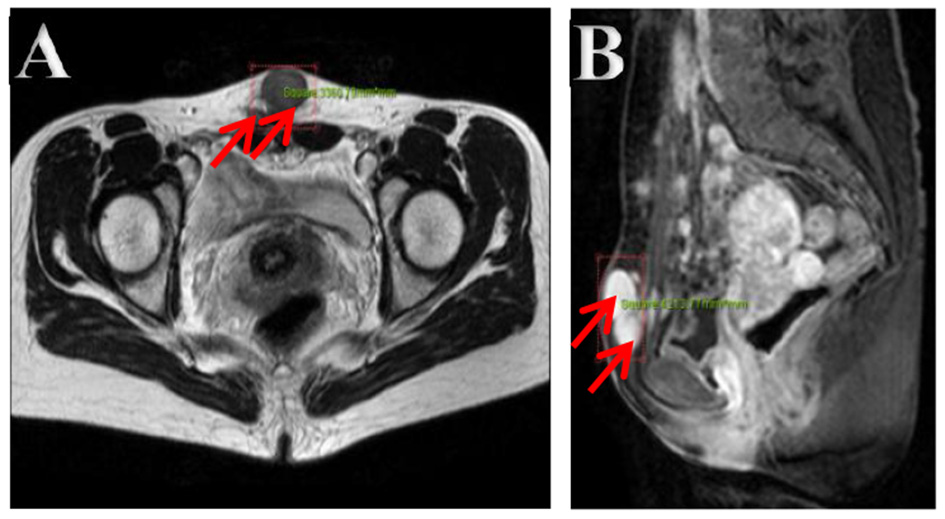

The ultrasonography showed a 1.5 cm × 1.8 cm × 1.5 cm hypoechoic mass in the posterior wall of the uterus and a 3.8 cm × 2.5 cm × 1.8 cm irregular mass behind the uterus. Color Doppler flow imaging (CDFI) showed a strip-like blood flow signal. In the subcutaneously muscular layer of the lower abdominal wall incision, there also were multiple solid masses with blood flow signal showed (Figures 1A–C). For further diagnosis, the pelvic enhanced MRI was performed, which showed surgical scar shadow in the anterior and lower abdominal wall. T1 and T2 low signal nodules could be seen in the soft tissue around the scar, in the right iliac fossa and behind the uterus. The larger one was located in the soft tissue of the abdominal wall, with a size of 2.6 cm × 1.7 cm × 2.8 cm. The enhanced scan was significantly enhanced but uniform. The size of uterus was normal without abnormal signal shadow found, and the enhancement was uniform (Figures 2A,B). A contrast-computed tomography (CT) scan of the chest also was performed. The texture of both lungs was clear, and the permeability of lung field was good. There was no enlarged lymph node shadow in mediastinum, and there was no abnormality in bilateral pleura and thorax.

Figure 2

(A,B) Pelvic cavity magnetic resonance imaging. Multiple nodes in the abdominal wall, in the right iliac fossa, and behind the uterus, with lower T1- and T2-weighted image. The bigger showed homogeneous enhancement on enhancement images in the soft tissue of the lower abdominal wall.